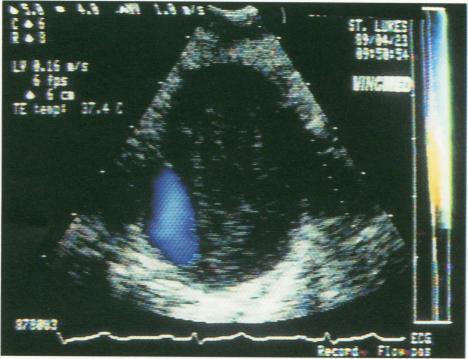

Transesophageal echocardiography in aortic dissection.

Aortic dissection is an emergent and potentially fatal condition requiring prompt and accurate diagnosis. In some patients, aortic dissection is abruptly painful at onset; in others, however, it has a chronic progression-with no apparent symptoms or with symptoms mimicking those of congestive heart failure. Transesophageal echocardiography, a promising new method for diagnosis of aortic dissection, has the advantages of being performed at the patient's bedside and providing results within 15 minutes. This method utilizes endoscopy and traditional noninvasive imaging techniques to provide a definitive picture of most segments of the aorta without the limitations associated with aortography and other invasive procedures. The technique of transesophageal echocardiography and its application in the diagnosis of aortic dissection are described in this report.